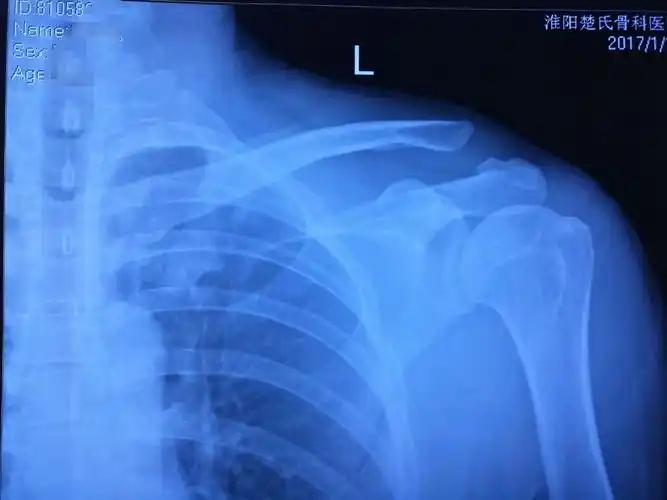

肩锁关节脱位关节镜微创复位固定

国际蒙医院骨伤科今日成功完成一例肩锁关节脱位肩关节镜喙锁韧带重建

临床带教案例-肩锁关节脱位

请问左肩锁关节脱位需要手术吗

肩锁关节脱位rockwoodⅥ型

骨伤一科成功完成我院首例endobutton带襻钢板治疗肩锁关节脱位手术

《肩锁关节脱位 》~肩部损伤 外五科 帮你恢复如常

我爸摔伤,可能是肩锁关节脱位,请问医生治疗方法和有什么影响不,谢谢

肩锁关节脱位治疗新进展

肩锁关节脱位手术治疗及康复第一周

右肩锁关节脱位纽扣钢板固定